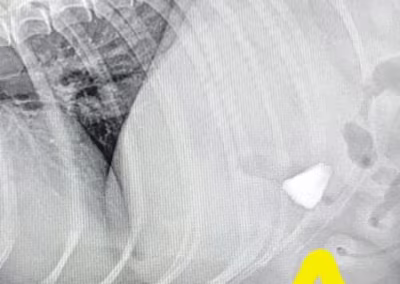

Na zdjęciu RTG widoczny był kamień, który został usunięty chirurgicznie.

Pikuś trafił do nas na RTG klatki piersiowej. Przy okazji odkryliśmy… pewien niespodziewany przedmiot 🙀🔍